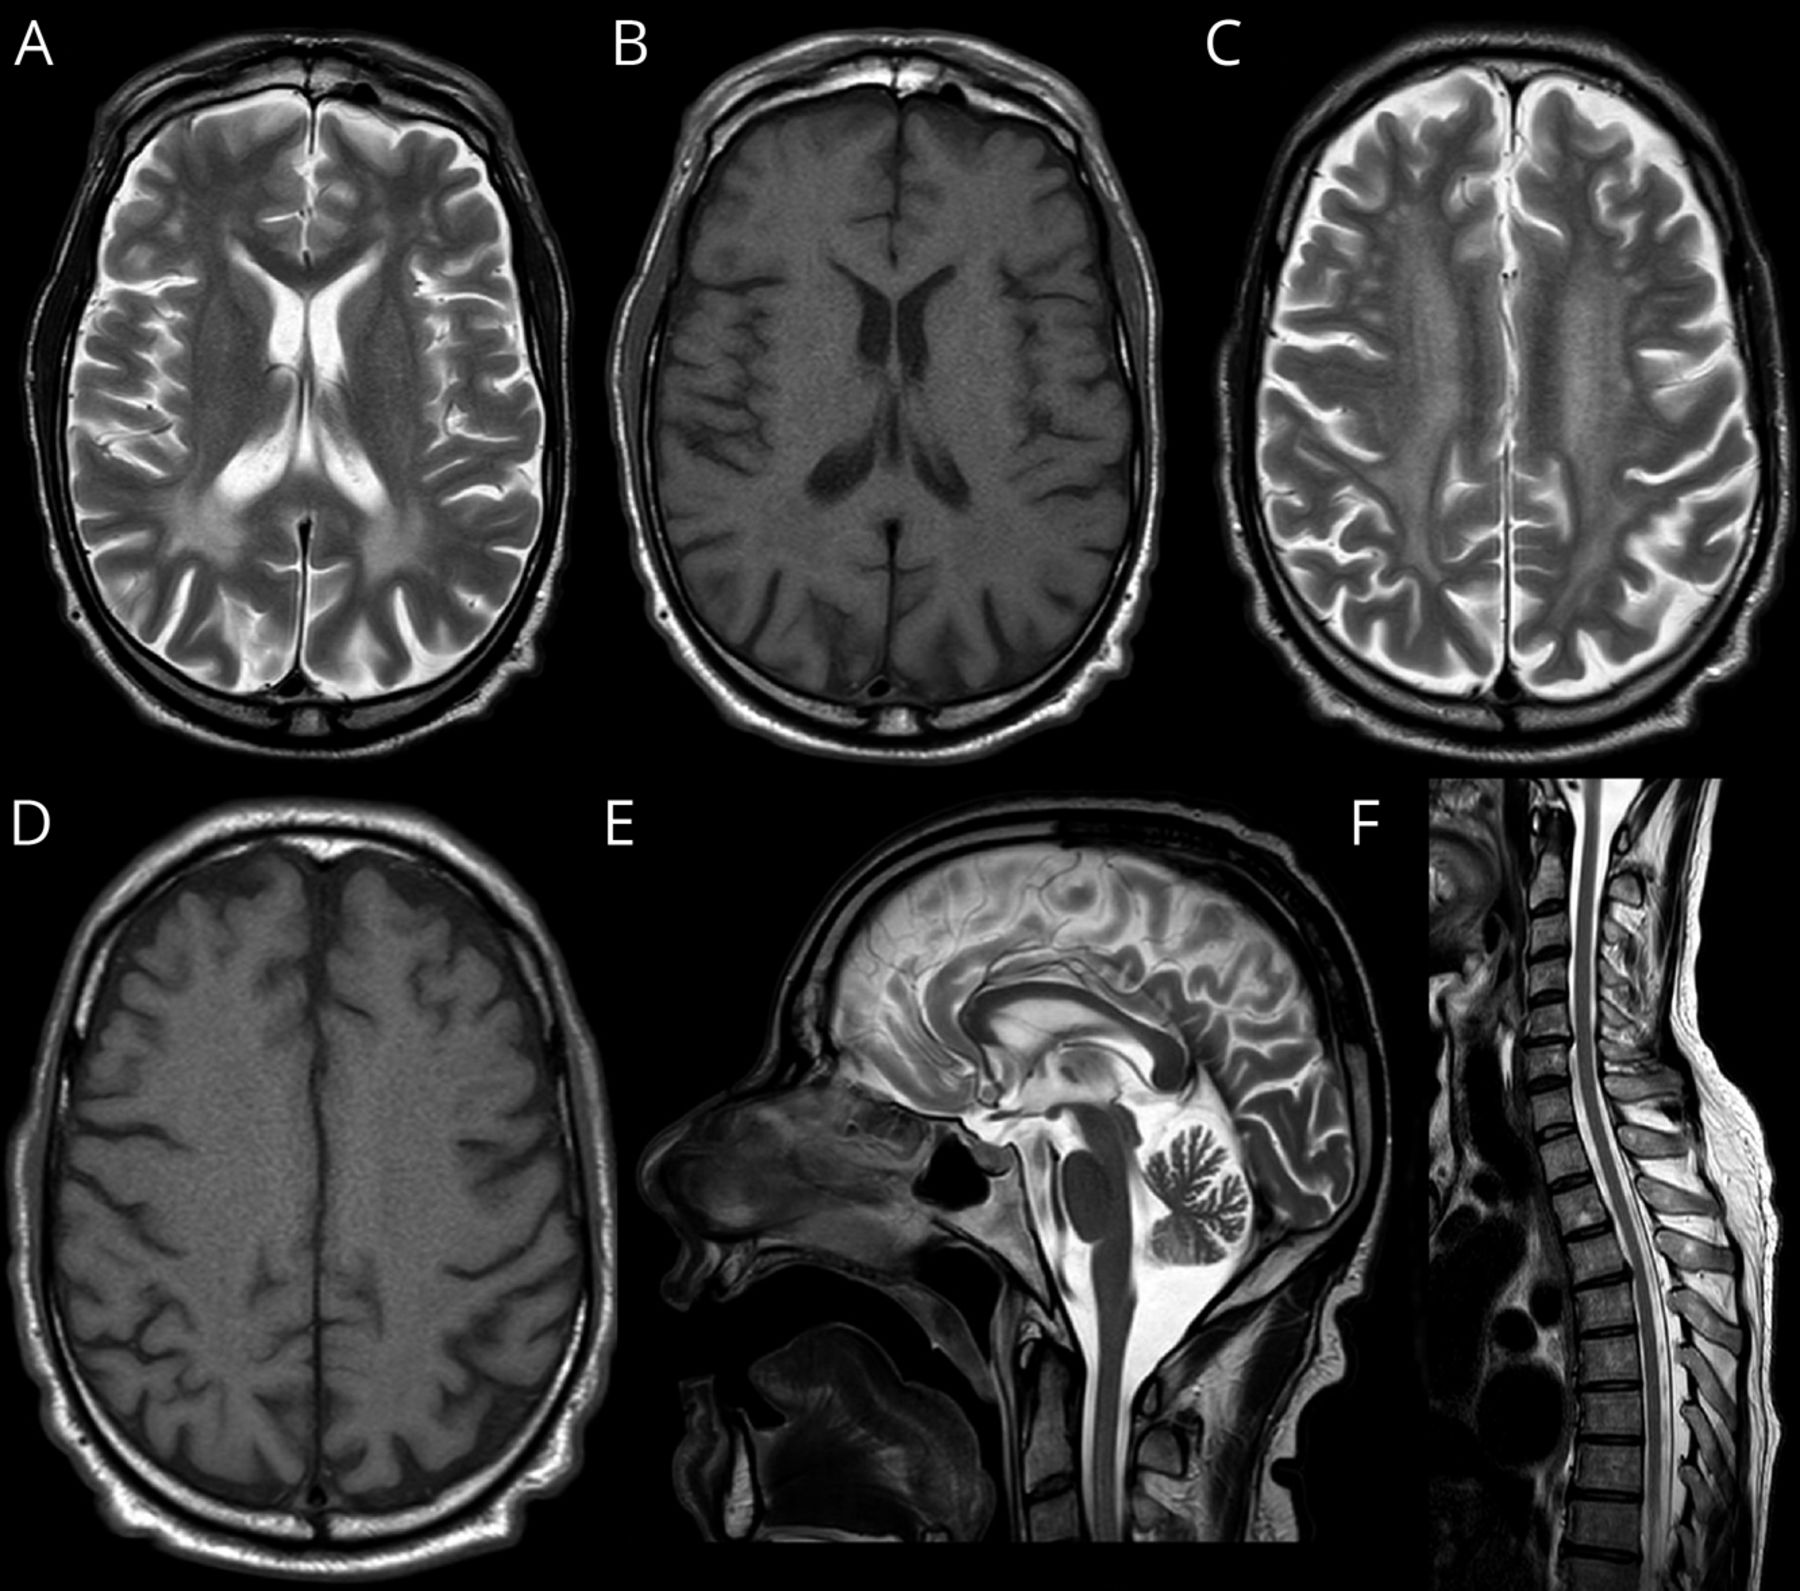

临床推理:一年轻男子亚急性发作痉挛性肢体麻痹